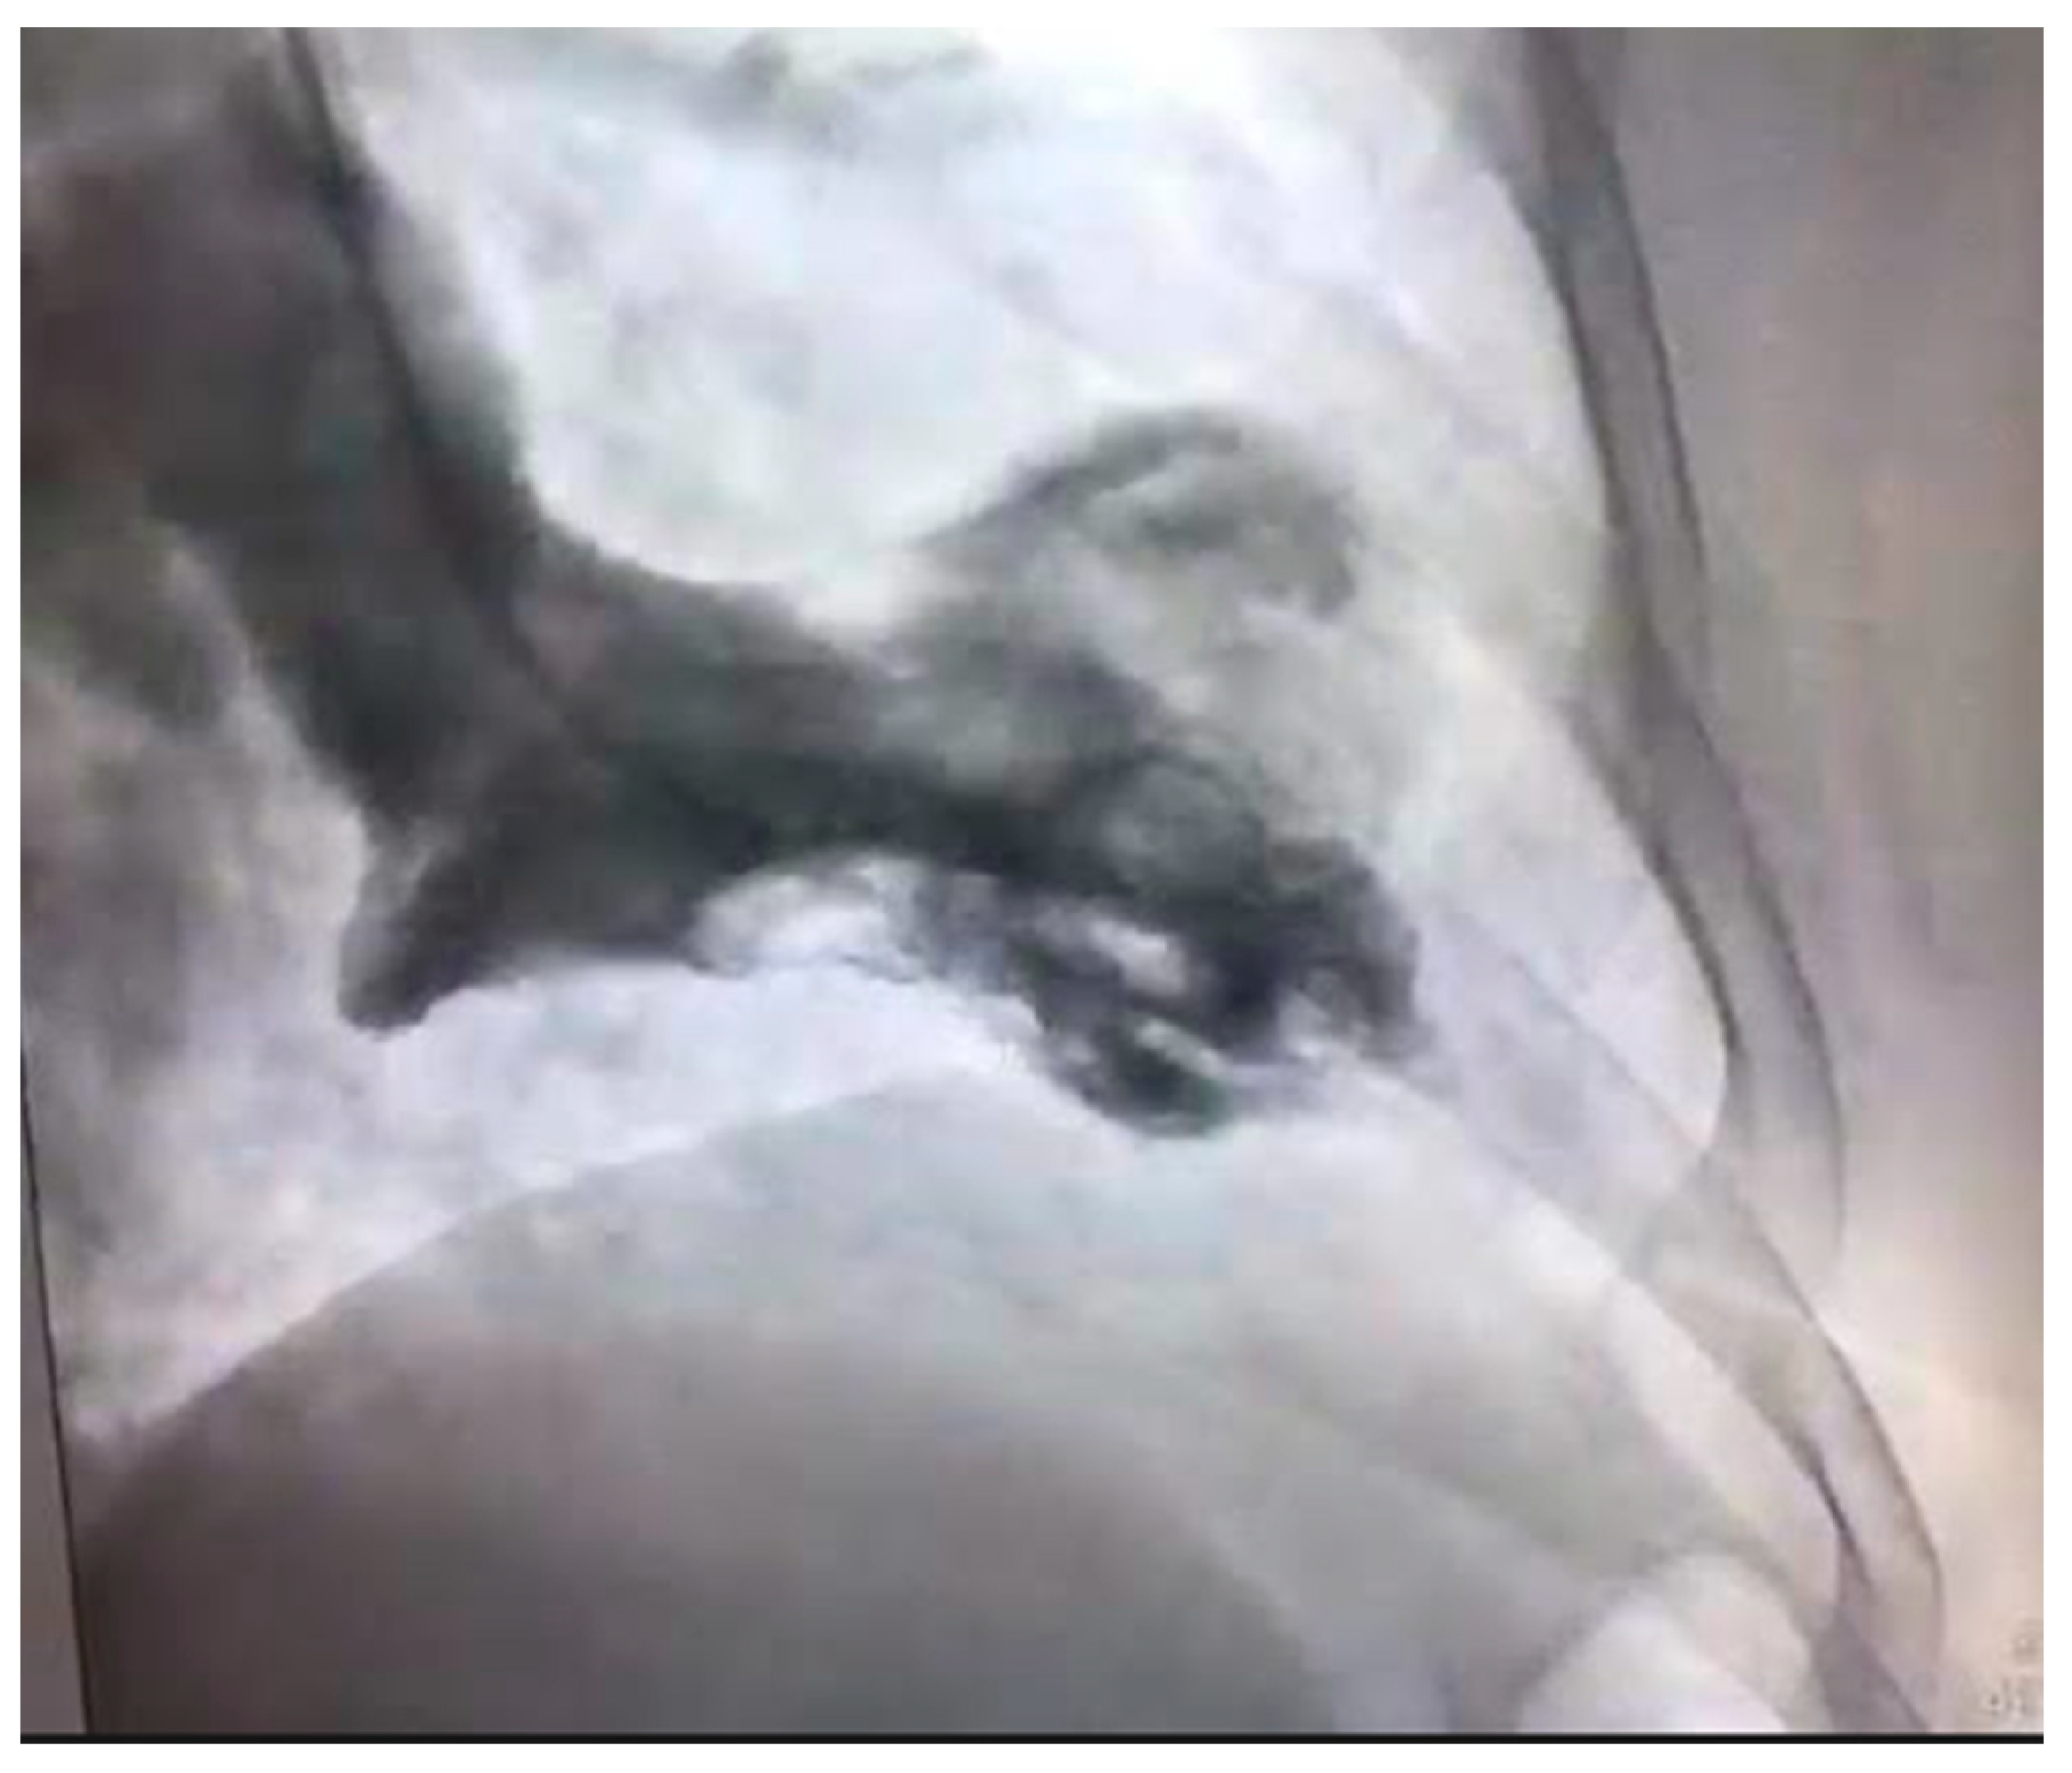

The differential diagnosis of MINOCA should include Takotsubo cardiomyopathy. This is a syndrome of transient ventricular apical ballooning (Figure 3). It has a female predilection with women accounting for over 90% of the cases [62]. The pathophysiology is catecholamine induced and not atherosclerotic in nature, although there is an increasing awareness of overlap syndromes of Takotsubo with CAD, with ACS playing a potentially causal role [63]. The pathophysiology of this syndrome is complex. The catecholamine surge causes a predominantly microvascular dysfunction—due to multiple factors including microvascular spasm and ensuring myocardial stunning, direct catecholamine cardio-toxicity, and an increase in the myocardial energy demand [64].

Figure 3.

Left ventricular angiogram in a 56-year-old patient with Takotsubo Cardiomyopathy.